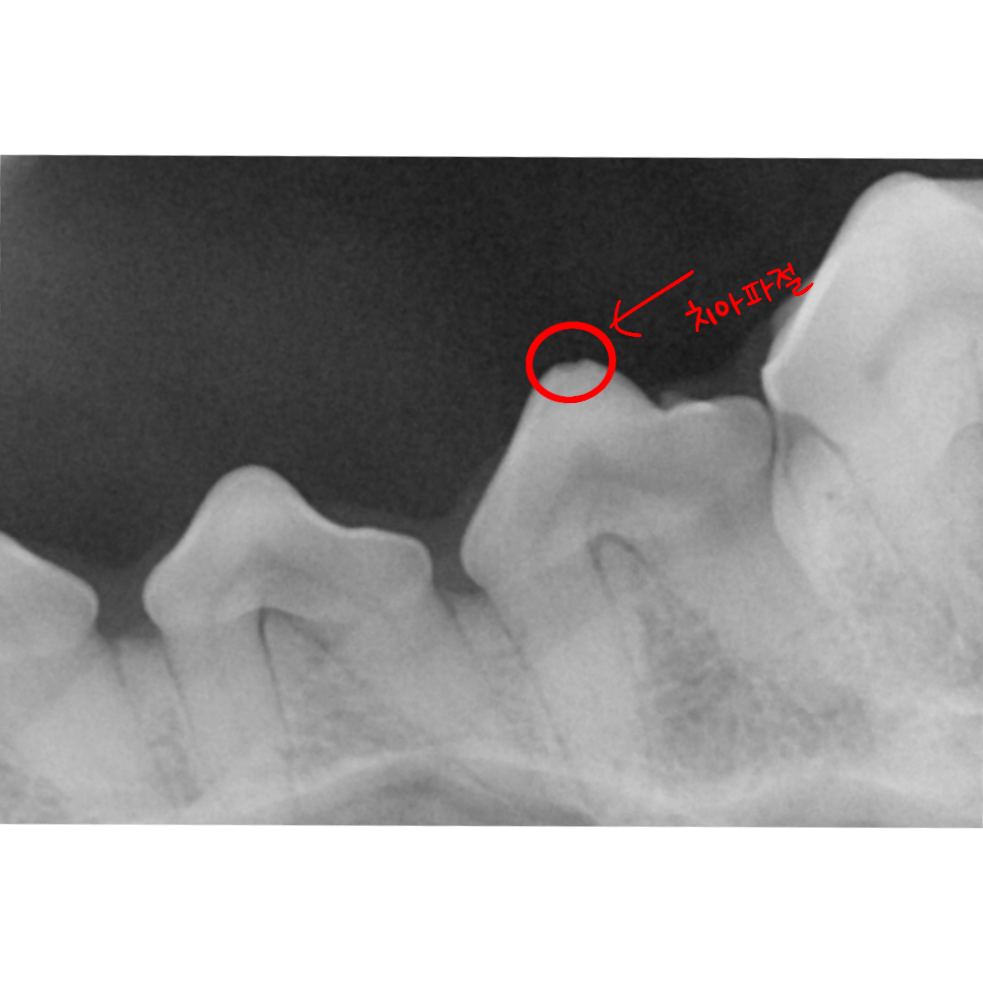

■ 강력한 교근(씹는 힘): 코기들은 무언가를 물고 당기고 뜯는 본능이 강합니다. 이때 발생하는 물리적 압박은 치아 표면의 미세 파절을 유발하고, 손상된 틈으로 치석이 파고드는 악순환을 만듭니다.

2.딱딱한 간식 금지령: 치아 파절 흔적이 있는 아이들은 이미 치아 에나멜층이 약해져 있을 가능성이 큽니다. 나무막대기, 플라스틱 장난감, 지나치게 딱딱한 개껌은 오히려 독이 됩니다. 손으로 눌렀을 때 약간의 탄성이 느껴지는 제품을 선택하세요.